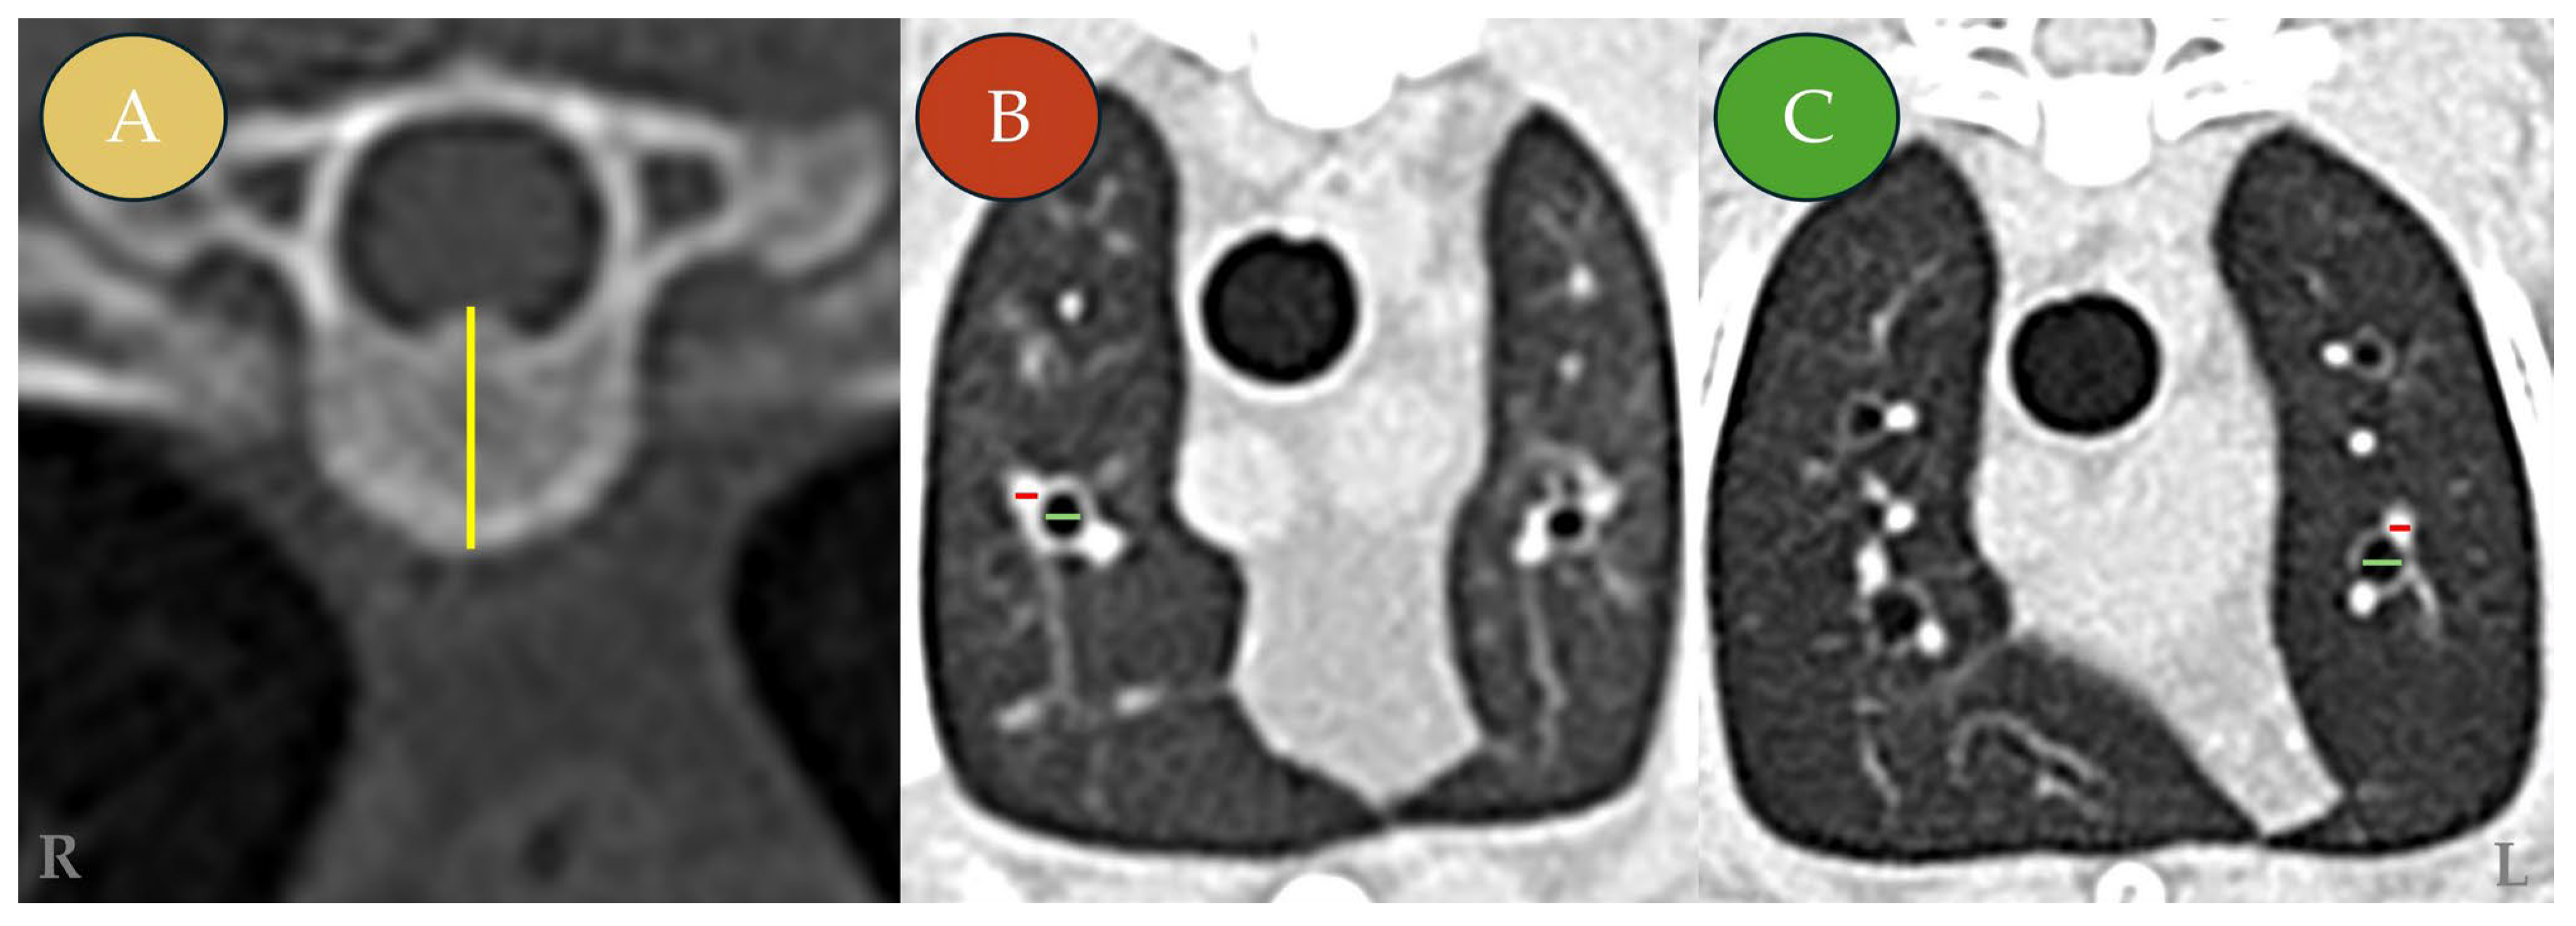

Bronchial and vascular luminal diameters were measured on axial images in which the structures appeared round or near-round, indicating a perpendicular orientation to the imaging plane. Minor cranial or caudal adjustments were allowed to ensure true transverse orientation, following previously described protocols [16,17]. The height of the sixth thoracic vertebral body (T6) was measured on axial images along its long axis, from the dorsal margin of the vertebral canal to the ventral cortical surface (Figure 1).

Figure 1. Representative transverse (axial) computed tomography (CT) images of symptomatic Dirofilaria immitis-seropositive cats (Group A). The images illustrate the morphometric measurement protocol for the vertebral body, pulmonary arteries, and bronchi. (A) Transverse (axial) section, showing measurement of the sixth thoracic vertebral body (T6) height (yellow line) performed along the long axis of the vertebral body, from the dorsal margin of the vertebral canal to the ventral cortical surface, and used for normalization. (B) Transverse section at the level of the T4–T5 vertebrae showing the right cranial lung lobe. (C) Transverse section at the level of T4–T5 showing the left cranial lung lobe (cranial subsegment). Measurement indicators: pulmonary artery diameter (red line) and bronchial luminal diameter (green line). L: left; R: right.